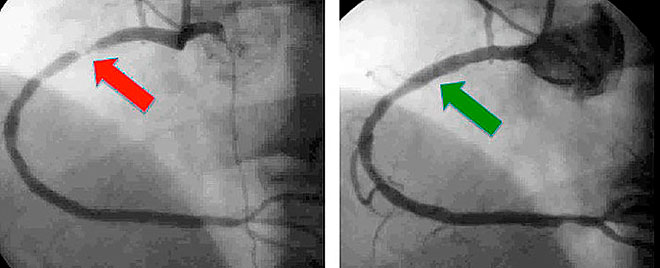

Атеросклероз занимает одно из лидирующих мест в рейтинге смертельных болезней. Залогом выздоровления и предотвращения развития сосудистых осложнений является выявление заболевания на ранней стадии. Коронарография является очень точным способом определения наличия атеросклеротических бляшек и их локализации. Исследование позволяет сделать вывод о степени тяжести и распространенности атеросклероза. Заключение результатов осуществляется с учетом следующих критериев:

- Степени сужения. Если по результатам диагностики просвет сосуда сужен менее чем на 50%, делается заключение о необструктивном коронарном атеросклерозе.

- Количества бляшек в артериях сердца. Число бляшек в одной, двух или трех сердечных артериях позволяет сделать заключение о количественном поражении лимфатической системы.

- Когда точно известно, что есть стенозирование коронарной артерии (сужение просвета атеросклеротическими бляшками), но нужно выяснить, насколько оно выражено. Рентгенхирурги глазами (то есть визуально) оценивают объем стенозирования. На экране можно увидеть «песочные часы, когда в месте стеноза проходящий контраст образуется сужение. Если это сужение совсем мало – тогда оценивают скорость, с которой смывается контрастное веществ (ведь следом за контрастом идет нормальный кровоток).